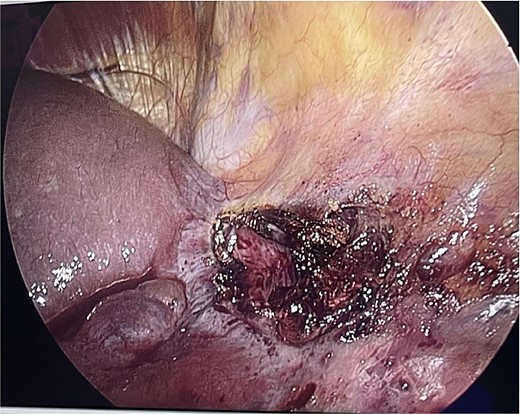

The patient was in the supine position (American position) and a Veress needle was inserted through a subumbilical skin incision and a pneumoperitoneum was created to 13 mmHg, after which a 10 mm optic trocar was inserted. Under optical control, another 5 mm trocar was inserted subxiphoidally and one 5 mm on the right mid-axillary line subcostally. Intraoperatively, a small whitish ribbon-like area was visualized in the area of the IVB segment with a length of ⁓3 cm/d. Using LigaSure, the Falciform ligament was resected for better visualization. Using a hook, the capsule of the cyst was opened and serous fluid was evacuated, which proved to be a simple cyst (Fig. 2). Cyst walls were excised down to the parenchyma using LigaSure. The cyst was visualized inside to rule out communication with the bile duct (Fig. 3). Due to the depth and intraparenchymal location, a drain was placed inside, which was removed on the 20th postoperative day until the drainage from the drain stopped completely. The total operative time was 40 min and the patient was discharged with a drain on the 2nd postoperative day. Pathomorphological examination of the removed cyst wall proved a simple cyst.